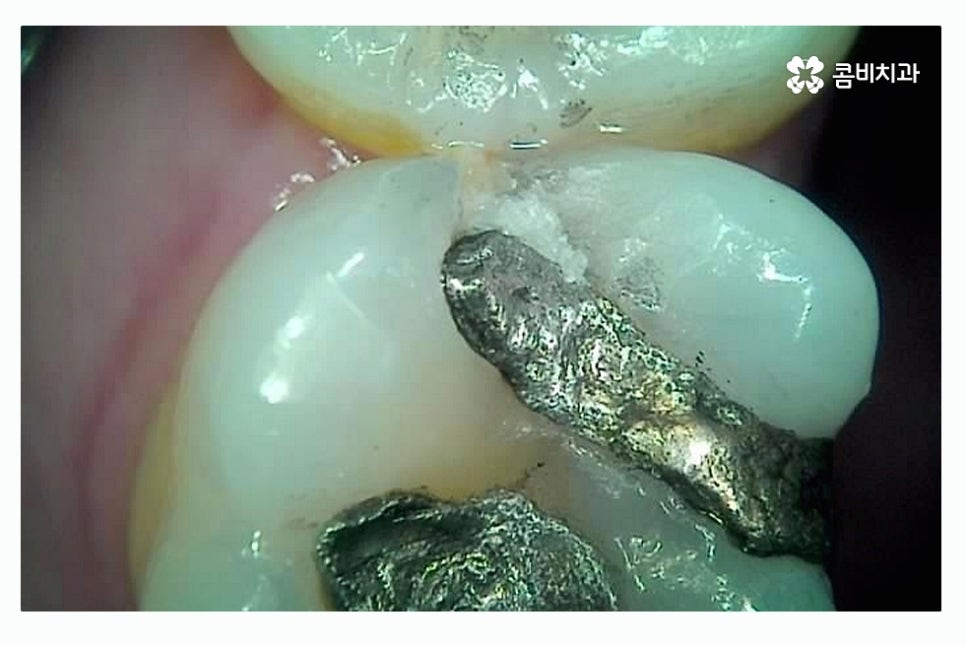

이미 과거에 충치 치료를 했던 레진, 인레이 안에 2차 충치가

발생되는 경우도 있기 때문에 이러한 사례의 경우

과거에 치료를 했던 레진, 인레이 혹은 아말감과 같은 치과용 치료 재료가

오랜 세월이 지나면서 마모, 접착 불량, 크랙 등의 이유로 교체가 필요한 시기에

치료가 안될 경우 치아 내부로 침이나 음식물이 유입이 되면서

충치가 발생하는 사례가 종종 있어요.